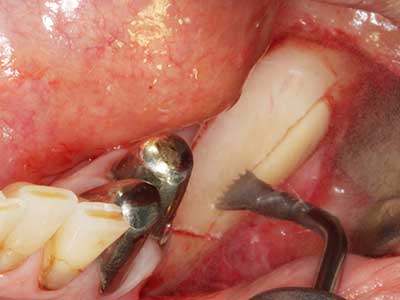

La piezochirurgia presenta altri vantaggi per quanto riguarda la raccolta di blocchi ossei. Oltre all'elevata precisione dell'osteotomia appena descritta, l'utilizzo di puntine per sega molto sottili permette di minimizzare in maniera significativa la perdita di materiale. È molto probabile che si verifichi una maggiore perdita di materiale durante la raccolta utilizzando puntine di strumenti più spessi, in particolare delle frese Lindemann (Lakshmiganthan, Gokulanathan et al. 2012). La separazione basale, necessaria in particolare per i trapianti di blocchi nella zona retromolare, viene semplificata grazie a seghe specificatamente progettate di forma rettangolare; di conseguenza la piezochirurgia è considerata una procedura precisa, semplice e sicura per la raccolta di blocchi di osso nella zona retromolare (Happe 2007) (figg. 1-12).

Indicazione: incisione ossea

Il tessuto osseo non è semplicemente una struttura minerale, ma contiene anche una percentuale significativa di fibre di collagene. Ciò significa che non possiede solo una buona forza di compressione, ma anche un certo livello di flessibilità che è possibile sfruttare durante l'esecuzione degli accrescimenti di osso. Nella procedura di espansione classica con incisione ossea, la cresta alveolare atrofizzata viene incisa longitudinalmente ed espansa con cautela dopo aver raggiunto una profondità di osteotomia adeguata (figg. 13-16), idealmente senza una sostanziale rimozione del periostio (Brugnami, Caiazzo et al. 2014, Stricker, Fleiner et al. 2014). I sistemi a piastra e vite con distanza di espansione incrementale si sono dimostrati efficaci nella separazione delle due lamelle ossee restando al di sotto della soglia di frattura. In generale, sono richieste larghezze dell'osso residuo di almeno 3-4 mm (Chiapasco, Zaniboni et al. 2006) per garantire un'adeguata flessibilità e una copertura sufficiente dell'osso per gli impianti futuri. Se necessario, un'osteotomia di rilascio verticale su uno o più lati può migliorare la flessibilità. Una combinazione con ulteriori tecniche di accrescimento, in particolare dal lato buccale, è stata descritta come un'alternativa alla tecnica classica.

La procedura di incisione è particolarmente atraumatica e non comporta una perdita significativa di dimensione durante l'utilizzo delle seghe piezoelettriche, così come non si notano differenze rilevanti tra impianti in mandibole incise e impianti in una cresta alveolare senza deficit osseo (Chiapasco, Zaniboni et al. 2006, Danza, Guidi et al. 2009). Una sufficiente irrigazione continua è essenziale, tuttavia, in particolare con incisione profonda e localmente ristretta, per prevenire la sollecitazione termica nelle regioni apicali dell'osteotomia.